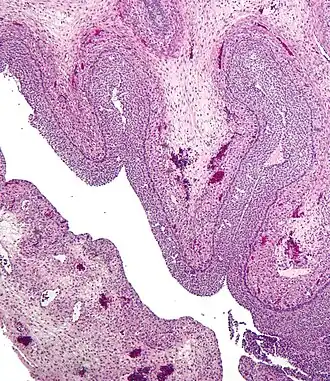

| Micrograph of a luteinized follicular cyst of the ovary. H&E stain. | |

This type can form when ovulation doesn't occur, and a follicle doesn't rupture or release its egg but instead grows until it becomes a cyst, or when a mature follicle involutes (collapses on itself). It usually forms during ovulation, and can grow to about 7 cm in diameter. It is thin-walled, lined by one or more layers of granulosa cell, and filled with clear fluid.